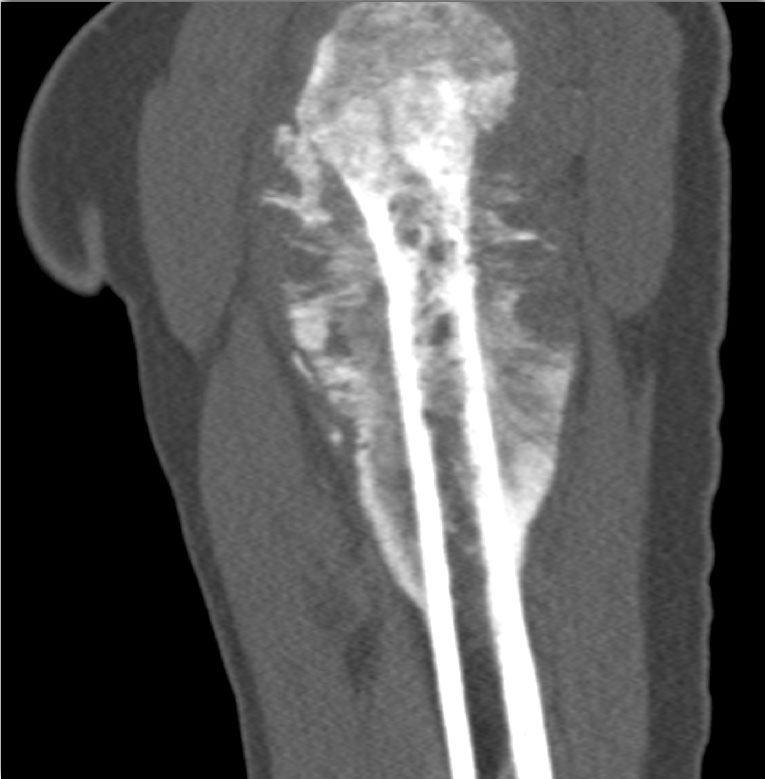

In this teenager with shoulder pain the best diagnosis is?

metastatic Wilms tumor

osteosarcoma

chondrosarcoma

lymphoma